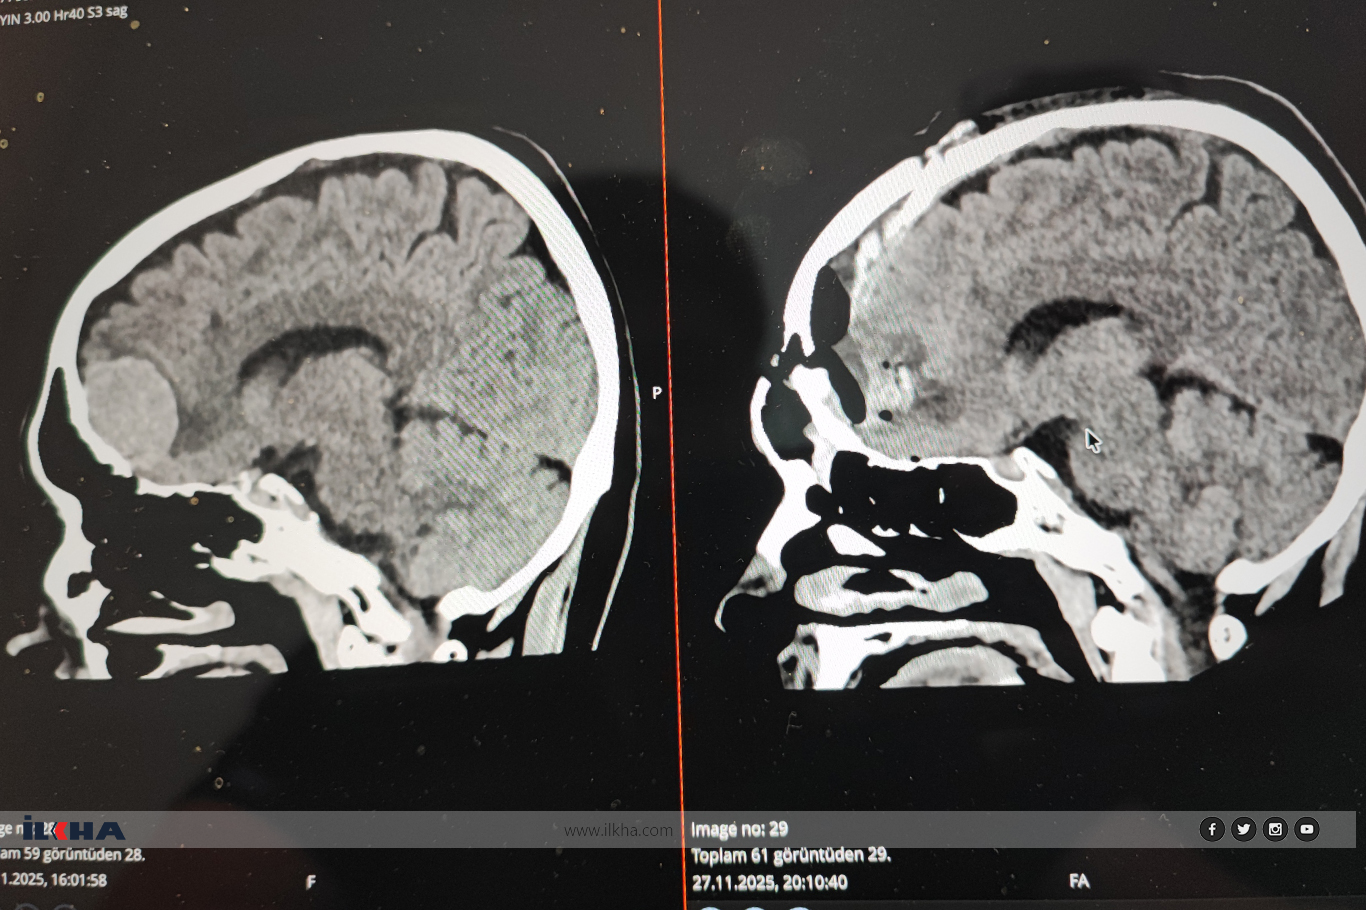

Karatoprak, erken müdahalenin birçok vakada hayat kurtardığını belirterek şu ifadeleri kullandı: "Epidural veya subdural kanamalarda saat değil dakikalarla yarışırız. Hasta bilinci kapalı gelebilir, yapılan görüntülemede kanama tespit edilirse hiç vakit kaybetmeden ameliyata alınması gerekir. Gecikme ölüm ya da kalıcı sakatlıkla sonuçlanabilir."